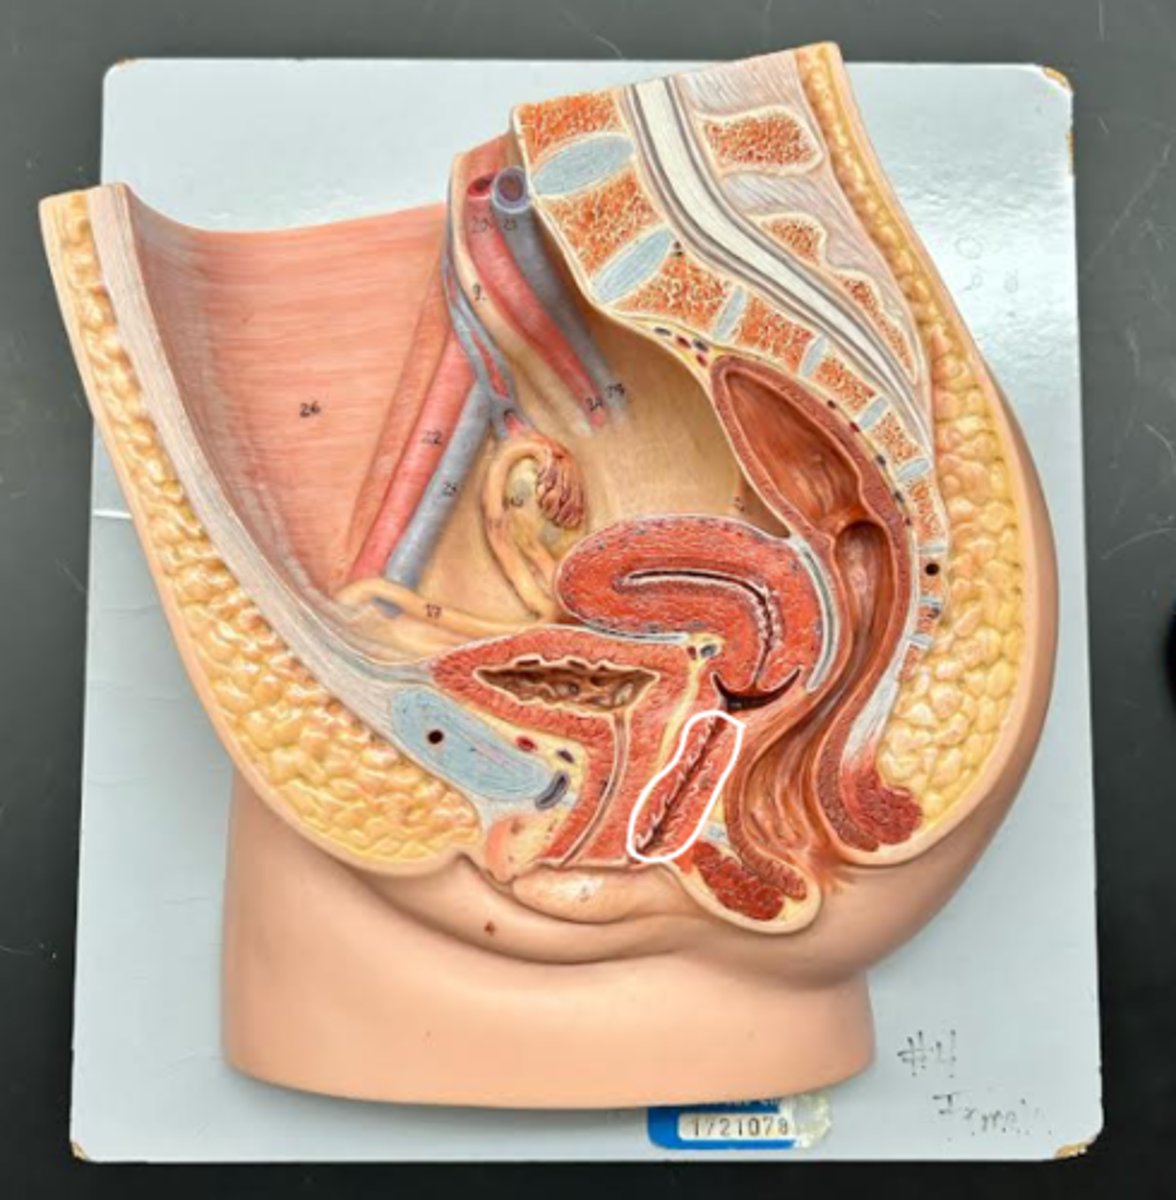

Vagina

Vaginal orifice

Hymen

Vaginal fornix

Cervix

Internal os

Cervical canal

External os

Labia majora

Labia minora

Prepuce

Vestibule

Clitoris

External urethral orifice